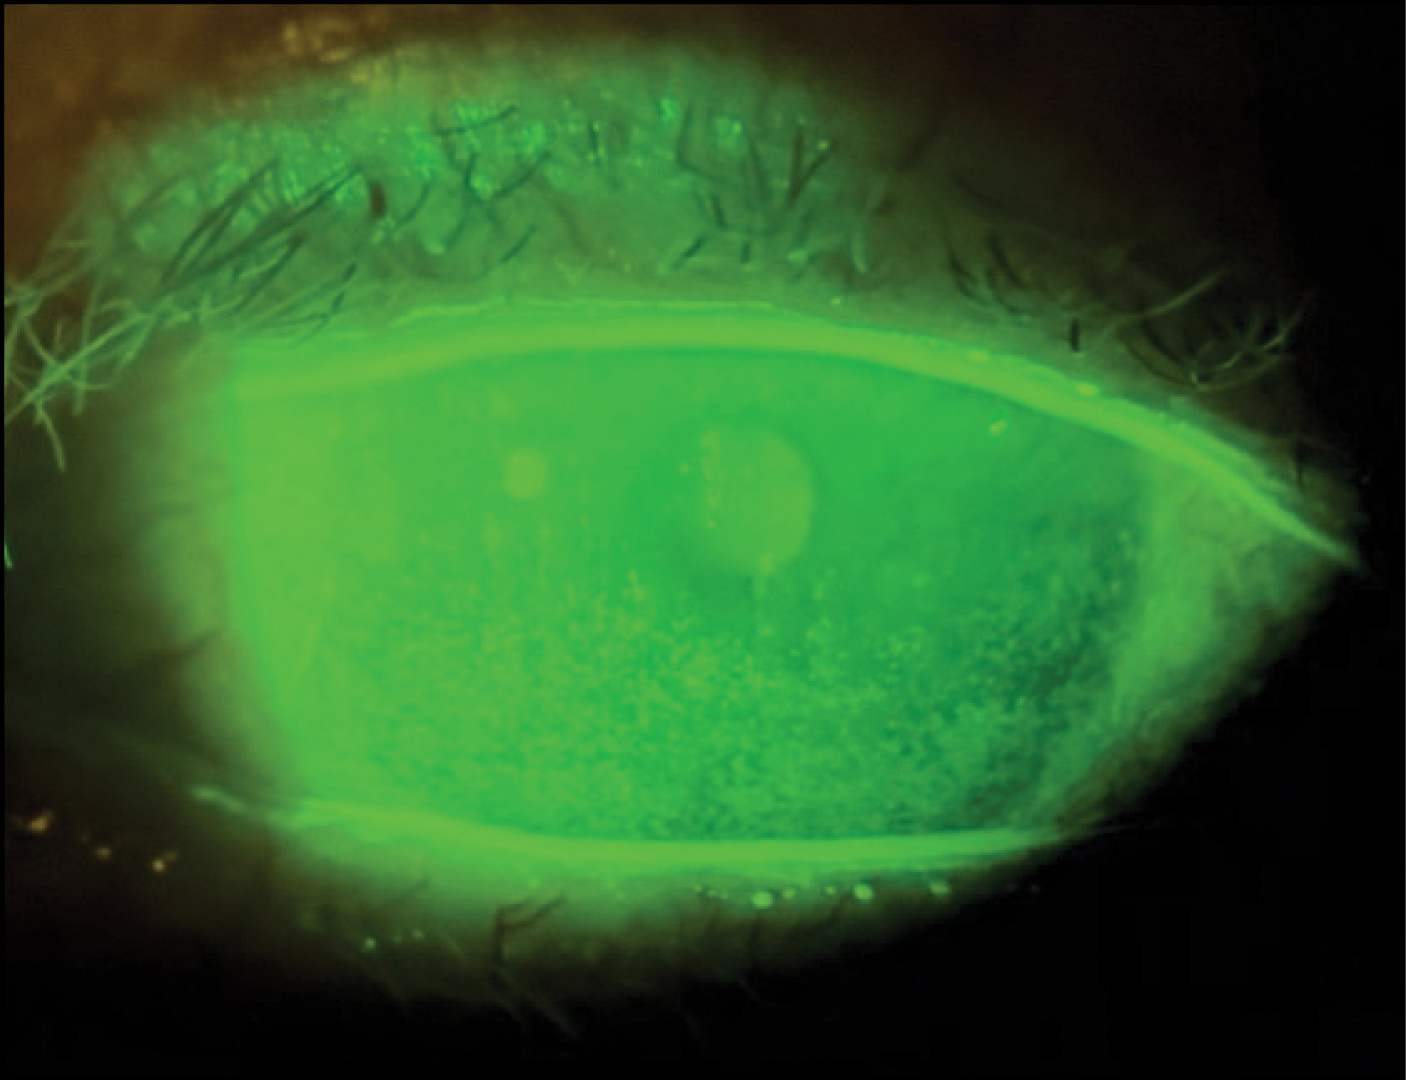

Secondly, using a 10-cent fluorescein strip gives me a wealth of information. I can assess the TBUT, look for corneal staining (Figure 8), examine the pattern of the dye across the surface, and check if there are any contributing lid abnormalities. I use the strip the same way every single time for all types of patients who come into my practice, and it has helped me to find the disease quite often.

Figure 8. Dr. Gupta uses fluorescein staining to assess the health of the ocualr surface.

Courtesy of Preeya Gupta, MD

Dr. Dierker: I agree with Dr. Gupta that we all need an efficient, reproducible protocol to screen for DED in each patient we see. It sounds like we all use targeted questions and look for symptoms, because DED is a symptomatic disease. We also look for loss of corneal homeostasis, whether that’s increased tear osmolarity or putting fluorescein in the eye and looking at the TBUT or ocular surface staining.